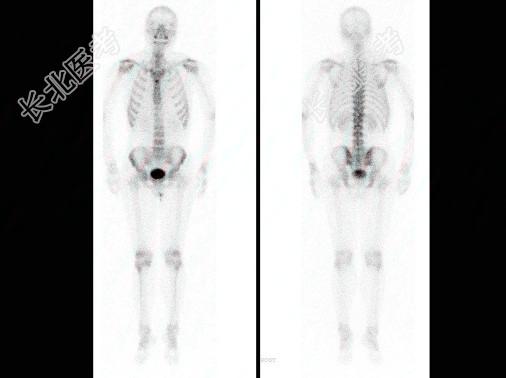

- 多项选择题男,肝癌术后1年, 诉腰背痛5个月,行全身骨显像如图, 碱性磷酸酶明显增高,可能的诊断是 ( )

A、胸12“冷区”

B、大致正常的骨影像

C、胸12骨转移瘤

D、胸12有溶骨性病变

E、肝癌骨转移“冷区”较常见